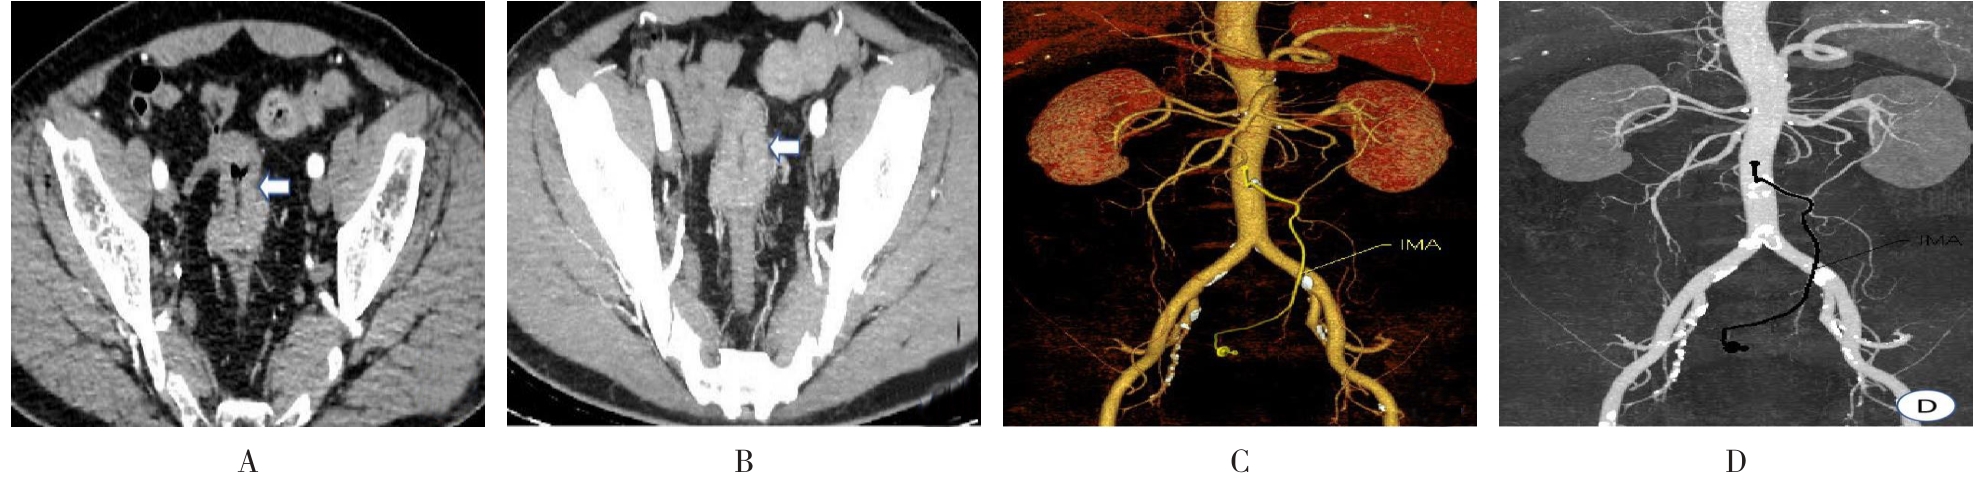

• 计算机体层摄影血管造影在腹腔镜结肠癌根治术前评估中的应用效果

2025, 31(6):24-31. DOI: 10.12235/E20240177

摘要 (181) HTML (147) PDF 4.65 M (171) 评论 (0) 收藏

摘要:目的 分析计算机体层摄影血管造影(CTA)在腹腔镜结肠癌根治术前评估中的应用效果。方法 回顾性分析2021年1月-2024年2月于该院接受腹腔镜结肠癌根治术的120例患者的临床资料。其中,60例行常规腹部CT和CTA,60例行磁共振成像(MRI)。以术后病理为金标准,判断CTA对临床T分期与术后病理的一致性,以及评估肿瘤是否侵犯肠系膜血管和周围组织的准确度。结果 术前CTA诊断T分期的准确率为95.00%(57/60),一致性好(Kappa = 0.925,P < 0.05);术前MRI诊断结肠癌T分期的准确率为98.33%(59/60),两者比较,差异无统计学意义(χ2 = 0.26,P > 0.05)。CTA预判肿瘤是否累及肠系膜上动脉、肠系膜上静脉、肠系膜下动脉、肠系膜下静脉、腹主动脉、肾动脉、肾静脉和脾动脉等血管,与术后病理的一致性好。特别是在预测肠系膜血管受累方面,CTA的敏感度为94.44%,特异度为95.83%,准确度高达95.00%。结论 对于行腹腔镜结肠癌根治术的患者,术前CTA不仅能清晰地显示结肠癌T分期,还能揭示肠系膜血管的走行和变异,以及肿瘤与周围组织的关系和侵犯程度,从而为手术规划提供强有力的支持,确保了腹腔镜手术的安全性,减少了不必要的手术风险。